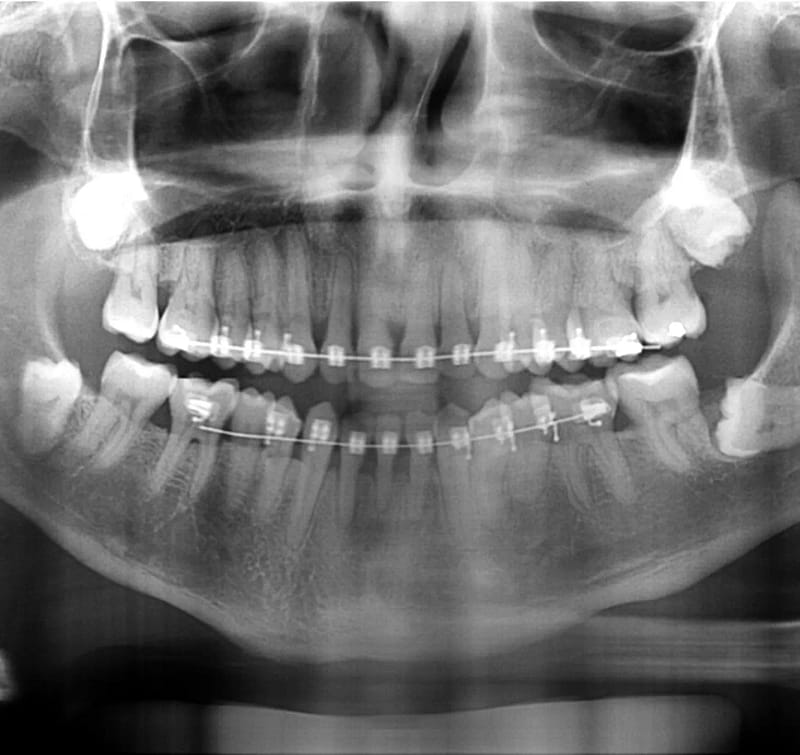

En Estudio Rx, entendemos la importancia de una evaluación dental precisa y completa. Es por eso que ofrecemos Radiografía Panorámica, un servicio esencial para un diagnóstico detallado de tu salud bucal. Este tipo de radiografía captura una imagen amplia de toda tu boca en una sola toma, mostrando todos los dientes, mandíbulas, y estructuras circundantes, desde las raíces hasta los huesos, de manera clara y detallada.

La radiografía panorámica es fundamental para detectar problemas como caries, fracturas, dientes retenidos, y patologías en las mandíbulas que pueden no ser visibles en una revisión convencional. Además, es una herramienta indispensable para planificar tratamientos complejos, como implantes dentales, ortodoncia y cirugías maxilofaciales, permitiendo que los especialistas tengan una visión completa de tu situación bucal.